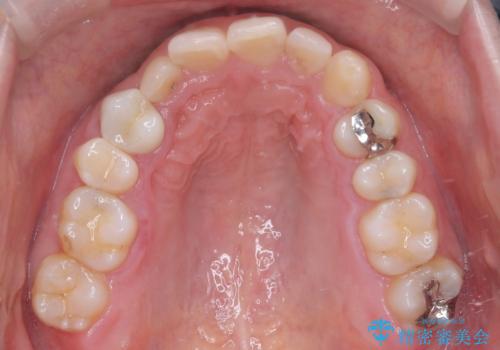

- 前歯の叢生(ガタつき)と、上下の噛み合わせが一部逆になっている反対咬合を主訴にご来院されました。精密検査の結果、前歯の移動だけでは不十分で、歯列全体のアーチを整えながらスペースを確保する必要があると診断。

中等度の症例に最適で最大26ステージ(※プランによる)のマウスピースが使用可能な**「インビザライン・モデレート」**を選択しました。これにより、抜歯をせずに歯列を横に広げ(側方拡大)、前歯を並べる十分なスペースを作りながら反対咬合を確実に改善する計画を立案しました。

反対咬合の解消: 内側に入っていた前歯を、マウスピースの力を利用して外側へ押し出しました。同時に、下顎の歯並びも微調整することで、スムーズに正常な噛み合わせへと誘導しました。